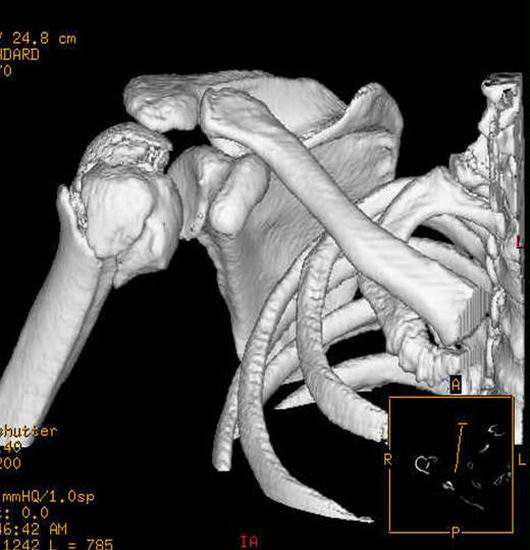

主要功能:全新东芝16层螺旋CT AqullionTM,具有超高分辨率的0.5毫米薄层图像,超长范围的快速扫描和世界上最快的0.40秒全周扫描速度,它代表着当今多层CT较高水平的尖端技术。